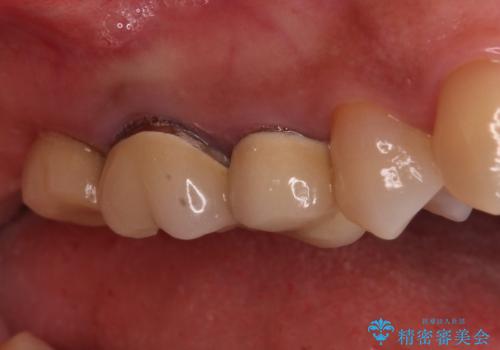

右上の一番奥の歯が欠損しており、その手前の歯2つを土台に連結されたクラウンが装着されていました。

不安定な咬み合わせとなっており、クラウンの表面が剥離していたため、インプラントによる欠損補綴治療を行い、手前2つの歯も一緒に補綴治療を行うこととしました。

治療中の仮歯も頻繁に壊れておりましたが、インプラントの土台が歯肉上に出てからは咬み合わせが安定し、仮歯が壊れることもなくなりました。